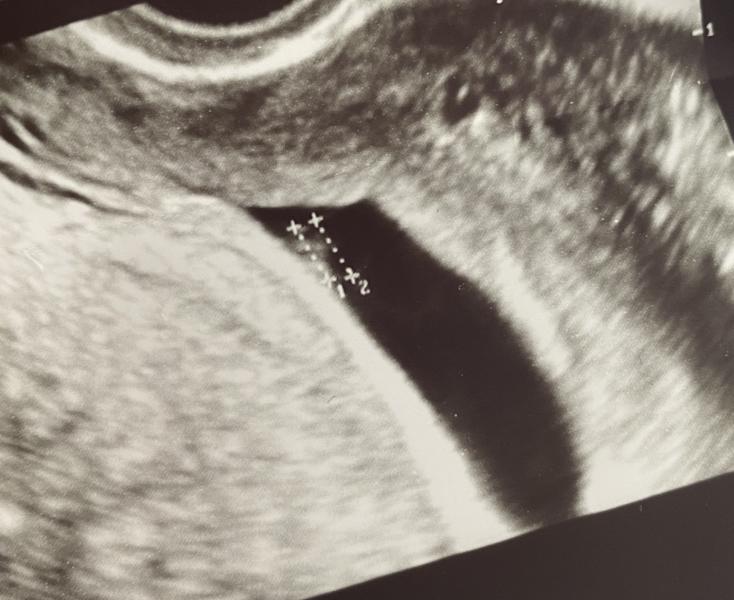

1.12 копчиково-теменной размер 2,73

9.12 копчиково-теменной размер 4,93